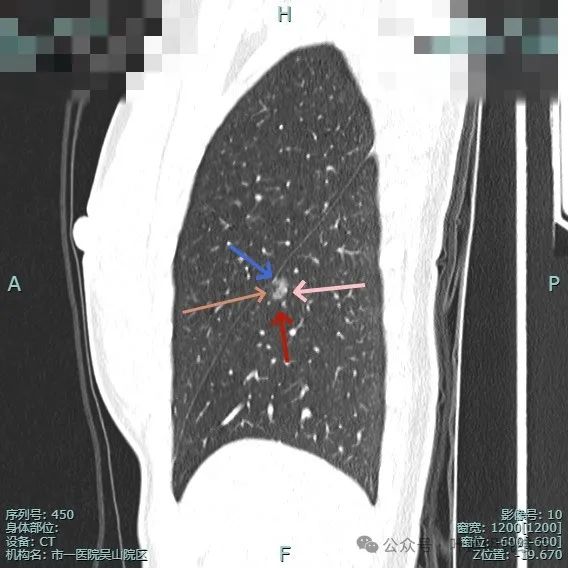

病灶表面不平有分叶与凹凸,密度也不均匀,有点状实性成分,邻近胸膜(叶间裂)。

表面有毛刺,灶内有小空泡征,边缘毛糙不平,密度显得不均匀。

部分边缘有毛刺或小棘突,病灶边上有扩张的细支气管,整体内部密度欠均匀。

边缘毛糙,血管进入,灶内密度显得杂乱。

有扭曲的血管进入血管,表面有凹陷与分叶。

密度不太纯,表面不平,血管有异常增粗。

胸膜有轻微牵拉,表面不平,多处微小血管进入,整体密度显得不匀。

血管征明显、灶内小空泡征、胸膜牵拉、边缘细毛刺征。

整体看上去密度不均、边缘不平、灶内空泡征以及细毛刺征均明显。